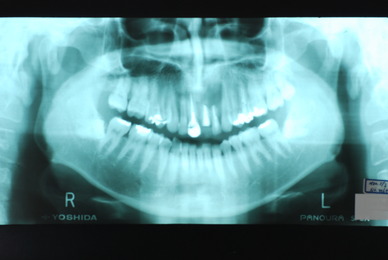

現実を見ればお口の中には“異物”である金歯、銀歯、セラミック、インプラントのオンパレードです。

これ等のものは、異物です。無い方が病気にならず健康でいられるのです。

その結果、歯科の潮流は保険にない、矯正や美容、インプラントぐらいしかやる気を出せなくなっているのです。

お口の中から差し歯、入れ歯、詰め物を追放しましょう!

必ずばい菌が侵入しないようにしてばい菌である虫歯を除去します。

銀歯の下はばい菌だらけです。こういうのはよくあります。取り残しですね。![treatment_05[1]](https://livedoor.blogimg.jp/netdental/imgs/3/a/3ad019d0-s.jpg)